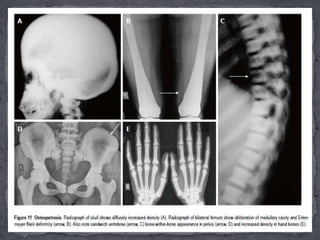

 The most severe form, termed as autosomal recessive

type is characterised by early onset of symptoms,

obliteration of medullary canals with bone marrow

failure leading to anemia, thrombocytopenia,

hepatosplenomegaly and early death.

 On other hand, in dominant form, the onset occurs in

adulthood with variable penetrance. These patients

have mild anemia and present more with fractures and

deformities.

Essential radiological features:

(1) There is diffuse sclerosis involving both the skull vault and

base with progressive narrowing of foramina causing cranial

nerve impingement, more so in the recessive type. In addition,

there is prognathism with predisposition to mandibular

osteomyelitis.

(2) In limbs, despite increased density, there are multiple

fractures. Fracture healing rate is normal but callus formation is

defective comprising of osteoporotic bone. In addition, there is

metaphyseal flaring leading to Erlenmeyer flask deformity.

(3) “Bone-within-bone” appearance typically noted in spine,

pelvis and short tubular bones. In spine, this is termed as a

sandwich vertebrae appearance due to endplate sclerosis and

relative lucency of centre of body. In pelvis, they appear as

multiple dense white lines parallel to the iliac crest .

Differential diagnoses include

 Pycnodysostosis.

 Craniotubular dysplasias.